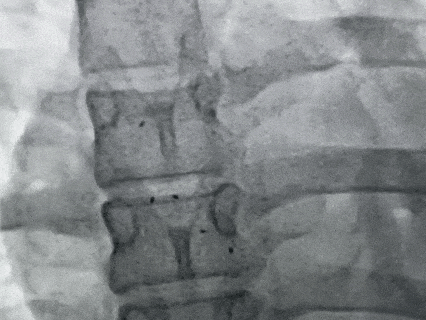

DSA下观察5个Mark点整体移动,封堵器形态良好,封堵成功